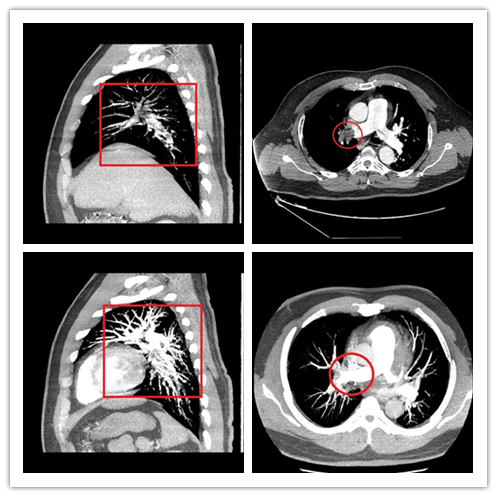

前段时间,刘先生因为肾结石做了取石手术。术后害怕活动影响恢复,出院后一直躺在床上,很少活动。7天后,刘先生感觉双腿胀痛,就去做了康复理疗,谁知道不但没缓解下肢疼痛的症状,反而感到胸闷胸痛,并且一直没缓解。在湖南省人民医院马王堆院区急诊二部就诊后,彭敏主治医师联合介入科、影像科多学科讨论诊断刘先生患有大面积肺栓塞,在完善了肺动脉CTA检查后,被确诊。专家们当机立断,紧急开放绿色通道,当晚安排紧急行下腔静脉滤器植入术+溶栓治疗术,手术不到两个小时顺利结束。刘先生在返回病房时生命体征平稳,胸闷好转,双下肢也不再胀痛。患者在术后第三天就恢复良好,康复出院。